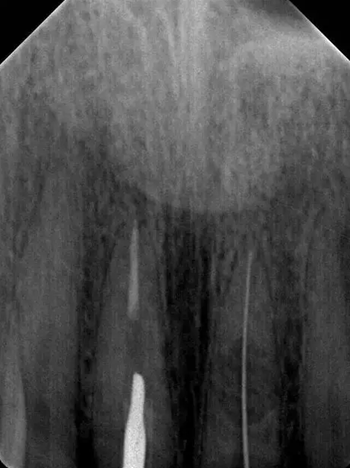

診斷:左上中切牙牙根內(nèi)吸收。治療計(jì)劃:左上中切牙根管治療,全冠修復(fù)。 治療過程:患者知情同意。使用含1/100,000腎上腺素的4%鹽酸阿替卡因(碧蘭麻,艾龍)局部浸潤(rùn)麻醉,橡皮障隔濕。去腐未盡露髓,露髓孔出血多。開髓,使用10#不銹鋼K銼(MANI,日本)探查根管,根管中段有鈣化物阻擋,不能達(dá)到牙根全長(zhǎng)(圖3A)。在顯微鏡下(Leica M400E,萊卡, 德國(guó)) 使用超聲尖(E1根管治療超聲尖,啄木鳥公司,中國(guó))通開,采用根管長(zhǎng)度測(cè)量?jī)x(Root ZX, Morita公司,日本)加診斷絲片法(圖1B)測(cè)量根管長(zhǎng)22 mm。使用控制扭矩馬達(dá)(X-smart,登士柏)和鎳鈦旋轉(zhuǎn)器械(Hero 642, Micromega)根管預(yù)備,根管預(yù)備過程中使用5.25%次氯酸鈉溶液沖洗。 根備完成后使用超聲蕩洗根管,5.25%次氯酸鈉溶液3 分鐘, 17% EDTA溶液1分鐘。干燥根管,使用螺旋充填器根管內(nèi)封氫氧化鈣糊,氧化鋅丁香油水門汀暫封。1周后患者復(fù)診,患者述無術(shù)后不適,檢查暫封完好,無叩痛,不松,牙齦無紅腫瘺管。使用橡皮障隔濕,去除暫封物,超聲蕩洗根管,5.25%次氯酸鈉溶液3 分鐘, 17% EDTA溶液1分鐘。干燥根管,牙膠尖(達(dá)雅鼎,中國(guó))和必蘭根充糊劑(Cortisomol, 艾龍公司,法國(guó))熱垂直加壓法根管充填。術(shù)后片顯示根充恰填,可見牙膠/糊劑被壓入鈣化物周圍和內(nèi)部縫隙內(nèi)

1月后復(fù)查無不適,行全瓷冠修復(fù)。8月2周后復(fù)查,患者無不適主訴,牙冠美觀,邊緣完好,患牙無叩痛,不松動(dòng),牙齦無紅腫瘺管, X線片示根周膜連續(xù),根尖周未見異常。建議患者避免用前牙撕咬食物,定期復(fù)查。 討論: 臨床上,由于牙根內(nèi)吸收和牙根外吸收的治療方法和預(yù)后不同,常需要對(duì)兩者進(jìn)行鑒別診斷。過去通常采用偏移投照的方法鑒別兩者。在偏移投照片上,外吸收病損和根管輪廓相對(duì)位置較正位片會(huì)發(fā)生變化,而內(nèi)吸收病損則不會(huì)[12]。